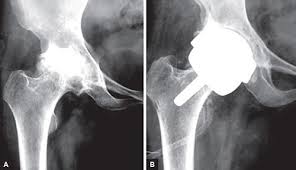

인공관절 수술은 원리에 따라 다양하게 나뉘며 닳아 없어진 무릎 연골 대신 인체에 해가 없는 코발트크롬, 티타늄합금 등의 금속이나 세라믹으로 만들어진 인공관절을 삽입하는 과정으로 진행된다고 한다. 다만 환자 입장에선 자신에게 적합한 수술법을 찾는 것이 더욱 중요해졌다고 한다.

3D 맞춤형 인공관절 수술은 다음의 과정으로 진행된다고 한다. 먼저 수술 1~2주 전 무릎 MRI 검사를 통해 무릎관절의 모양•크기 등 구조를 측정한다고 한다.

그리고 3D 시뮬레이션으로 가상 수술을 집도해 인공관절을 어디에 어느 각도로 넣을지를 분석한다고 한다. 이를 기반으로 환자 개인의 맞춤형 수술 도구를 3D프린터로 전송해 출력한다고 한다.

완성된 출력물 즉, 관절 절삭 부위를 알려주는 ‘PSI(Patient Specific Instrument)’라는 절삭유도장치라고 한다. 수술 시 손상된 관절 부위에 PSI를 끼우고 망가진 관절을 잘라내면 인공관절이 정확한 자리에 이식된다고 한다.